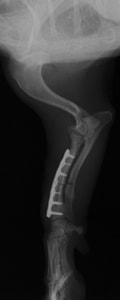

症例:柴犬 3歳

左後肢の完全挙上を主訴に来院されました。触診にて近位足根関節の過伸展を、レントゲン検査にて左足根関節周囲の軟部組織の腫脹、ストレス撮影によって距骨・踵骨と第4足根骨・中心足根骨間の脱臼および過伸展を認めました。

術中において、浅趾屈筋腱を剥離、内方へ牽引し、直接踵骨から第4足根骨までピンを挿入し(あらかじめ細いピンで下穴をあけておくとよい)、テンションバンドワイヤー法を併用し、関節軟骨の掻爬と海綿骨移植を実施しました。

術後レントゲン画像上に癒合が認められるまで約2ヵ月間は、運動を制限する必要があります。

術前側面像屈曲位